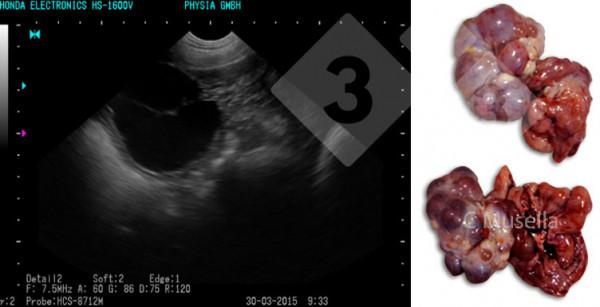

單個或多個卵巢囊腫的診斷相對簡單,即使透過超聲影象對囊腫型別的完全鑑別並不總是確定的。

近年來的研究也證實了超聲在排卵前後卵巢結構顯示和卵巢病理診斷中的有效性。

5、不孕症和病理病例